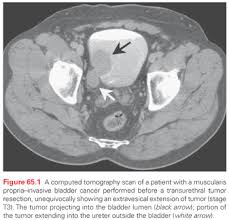

Get Stage 4 Bladder Cancer Ct Scan Pictures. For bladder cancer, the stage is determined based on examining the sample removed during a turbt (see diagnosis) and finding out whether the clinical staging is based on the results of tests done before surgery, which may include history, physical examinations, imaging scans, and biopsies. Like ct scans, mri scans show detailed images of soft tissues in the body.

Patients who have been diagnosed with stage iv cancer may consider getting a second opinion to confirm the diagnosis and explore treatment options. It may also have spread to lymph nodes and distant sites in the body. You may be offered a ct scan or an mri scan if the specialist feels they need a more detailed picture of your bladder.

Therefore computer aided diagnosis can be helpful for doctors to identify the cancerous keyword: See all parts of this guide hide guide parts. A ct scan provides a the outlook for bladder cancer patients depends on the stage of cancer at the time of diagnosis. Bladder cancer begins when cells in the urinary bladder start to grow uncontrollably.